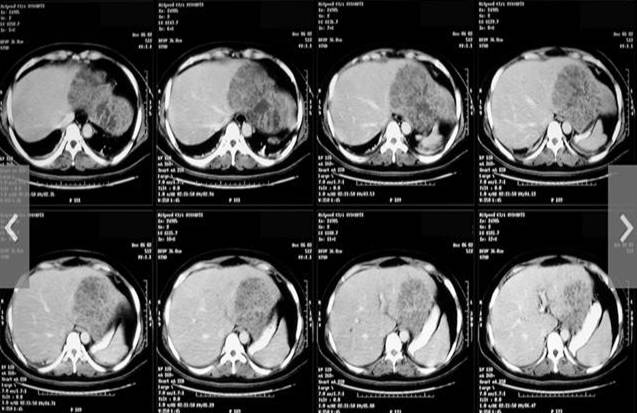

Hình 2

Việc chẩn đoán bệnh sán lá gan lớn ở người thường dựa vào phổ lâm sàng và xét nghiệm gồm có soi tìm trứng sán trong phân (song việc phát hiện trứng sán thường hiếm khi thành công vì người không phải là vât chủ chính), xét nghiệm huyết thanh miễn dịch ELISA hoặc Western blot (chỉ thực hiện tại một số bệnh viện hoặc trung tâm y tế chuyên khoa), siêu âm, chụp cắt lớp vi tính và chụp cộng hưởng từ được áp dụng phát hiện tổn thương là những công cụ chẩn đoán thường quy tại nhiều cơ sở y tế, giúp phát hiện và chẩn đoán tổn thương sán lá gan lớn rất hiệu quả. Để nhiều đồng nghiệp quan tâm đến bệnh sán lá gan lớn một cách tổng thể nhất, đặc biệt là phương diện chẩn đoán hình ảnh.